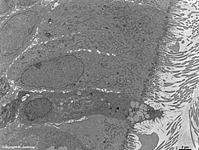

Miniaturbildübersicht Rachenmandel (Tonsilla pharyngealis) des Menschen:

Epithelzellen mit durchwandernden

Lymphocyten (Mensch)

Die Rachenmandel (Terminologia histologica: Tonsilla pharyngealis; englisch: pharyngeal tonsil) befindet sich im obersten Teil des Rachens (Epipharynx) und gehört mit den anderen Mandeln (Tonsilla palatina, - lingualis und tubaria) zum Waldeyer'schen Rachenring, der bei der Infektabwehr der oberen Luftwege eine wichtige Rolle spielt. Sie zeigt ein typisches respiratorisches Epithel (= Flimmerepithel: mehrreihig mit hochprismatischen Zellen; Terminologia histologica: Epithelium respiratorium; englisch: respiratory epithelium). Neben den Kinozilien und Mikrovilli tragenden Zellen, gibt es andere, die nur Mikrovilli an ihrer Oberfläche zeigen und einige Becherzellen. An einigen Stellen stülpt sich das Epithelin die Tiefe ein, wodurch Krypten entstehen. In der obersten Schicht, der Lamina epithelialis, finden sich neben den ebengenannten mit Fleckdesmosomen (Maculae adhaerentes) aneinander befestigten Epithelzellen noch an verschiedenen Stellen durch das Epithel in Richtung Rachen wandernde Lymphocyten und Mikrophagen, diese weisen keine Desmosomen auf. Darunter befindet sich als nächste Schicht die Lamina propria aus lockerem Bindegewebe in welchem sich Lymphfollikel (rundliche Ansammlungen von Lymphozyten) finden. Die tiefer liegende, schwach ausgebildete Bindegewebskaspsel ist mit dem umliegenden Bindegewebe verwachsen.